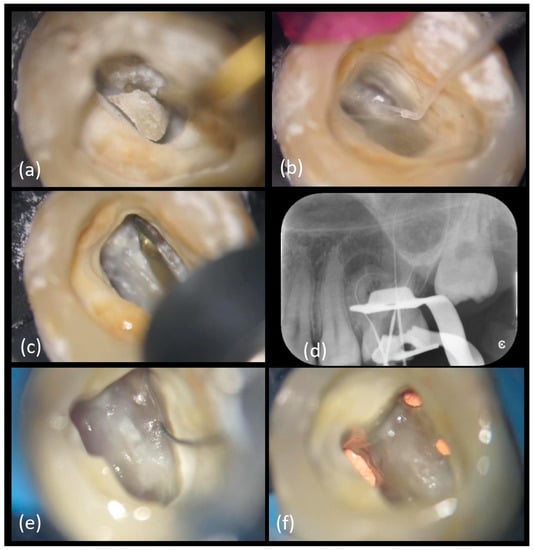

Treatment procedure: Root canal treatment was performed under local anestesia, articaine hydrochloride with 1:100,000 articaine (Septodont, Saint-Maur-des-Fossés, France) and rubber dam (VISION rubber dam, ASA DENTAL, Bozzano, Italy) isolation. The access cavity was opened mimicking the preliminary design on 3D-model, under operative microscope. Ultrasonic tips were used to remove pulp calcifications and to finish the access cavity (Figure 8a).

Figure 8.

Main clinical steps of case 2. (a) Access cavity with US tips, (b) chamber irrigation with IrriFlex®, (c) orifices enlargement with TruNatomy™ Orifice Modifier followed by the TruNatomyTM series, (d) working lengths X-ray control, (e) MB2 location and (f) filling with bioceramic sealer and single cone gutta-percha technique.

After the Micro-Opener 10.04 use andchamber irrigation, (Figure 8b) the orifices were enlarged with a TruNatomy™ Orifice Modifier 20.08 (TOM) (TruNatomy™, Dentsply Maillefer, Charlotte, VA, USA) (Figure 8c) (Movie 9). A temporary filling (Fuji IX, GC Italia, Milan, Italy) was placed following dressing with calcium hydroxide.

At the second appointment a viscous chelator (GLYDE File Prep Intro Package, Dentsply Sirona, Charlotte, VA, USA) was employed to facilitate the negotiations of the canals and the displacement of the dentinal shaving to minimize the risk of blockages.

The canal was progressively negotiated to full patency with a 10/.02 K-file. Working lengths were confirmed with an electronic apex locator (Root ZX mini, Morita, Tokyo, Japan) and a periapical X-ray (Figure 8d) as follows: MB1 was 27 mm long, MB2 merged with MB1 (Figure 8e), distal and palatal canals were respectively 30 and 28 mm long.

TruNatomy™ Glider 17/0.02 was used to obtain a rotary reproducible glide path with a mini-invasive approach, followed by TruNatomy™ Small 20/.04, as recommended for small canals. Afterwards, all the canals were prepared up to TruNatomy™ Prime 26/.04.

The irrigation protocol consisted of the following:10 mL of 5% sodium hypochlorite, used between each file of the TruNatomy™ series with sonic activation through a cordless unit with a flexible tip; 2 mL of 17% ethylenediaminetetraacetic acid (EDTA 17%, OGNA) for 60 min with sonic activation (EndoActivator®, Simit Dental, Maillefer, Charlotte, VA, USA) and a final rinse for 90 min with 5% sodium hypochlorite and 60 min of sonic activation (EndoActivator®, Simit Dental, Maillefer, Charlotte, VA, USA). Between each solution change and at the end of the irrigation protocol a sterile saline solution, Sodium Chloride 0.9%, was used.

Considering the anatomical complexity, the minimal preparation and the good result obtained with the mock obturation on the 3D-model, a single cone technique with TruNatomy™ Conform Fit™ Gutta-Percha Prime 26/.04 was chosen and combined with a bioceramic sealer (EndoSequence BC Sealer HiFlow, Brasseler USA®, Savannah, GA, USA) which is flowable and can fill any irregularities or voids (Figure 8f) (Movie 10). The coronal anatomy was restored with a build-up, followed by an indirect composite overlay. A post-operative LCPA X-ray was taken (Figure 9a). Clinical and radiographic follow-up was scheduled at 6 months: the patient confirmed that the tooth had been clinically asymptomatic and periapical X-ray showed a smaller radiolucent area around the mesial buccal root (Figure 9b); closure of the existing sinus tract was observed too. The next follow-up has been planned at one year.